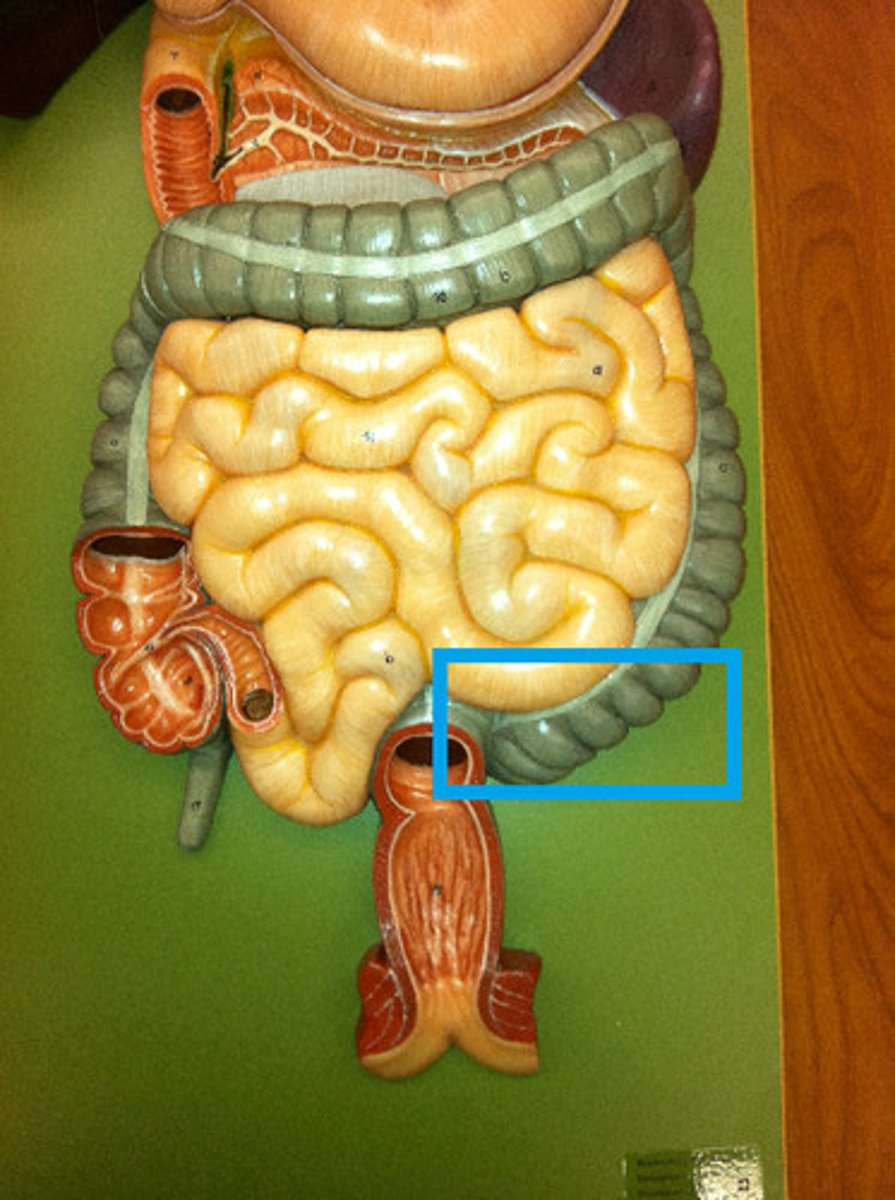

small intestine

duodenum

A

jejunum

B

ileum

C

large intestine

cecum

ascending colon

transverse colon

descending colon

sigmoid colon